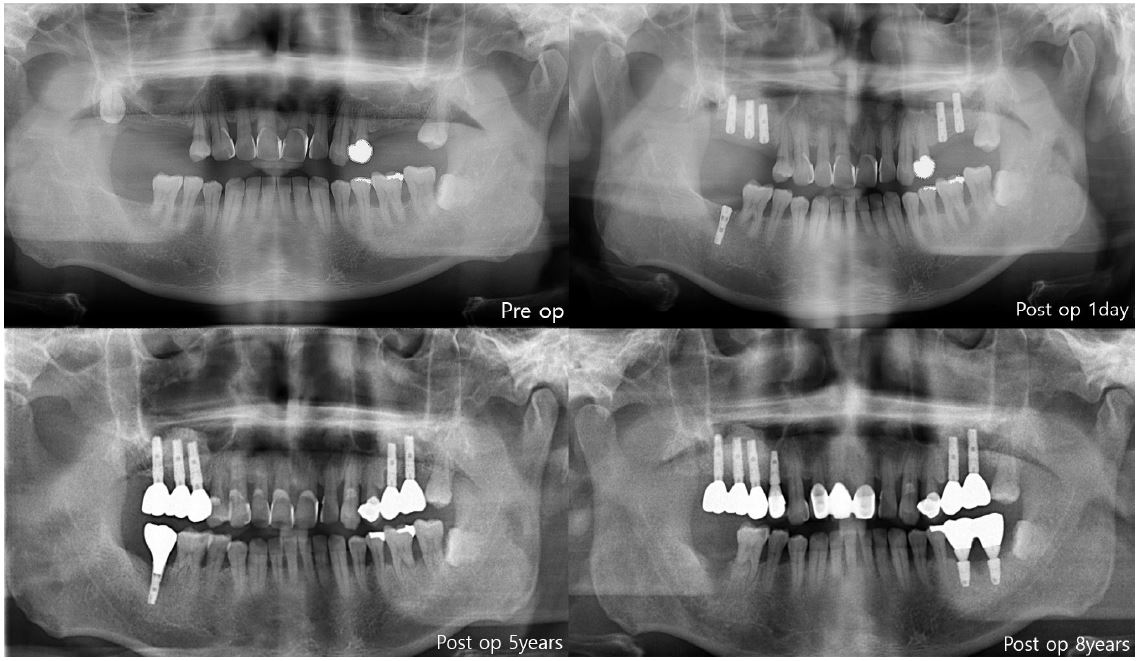

In the first case of failure, the patient had no specific medical history. The implant was removed at 6 years and 11 months (Fig. 3). In the second case, the patient had diabetes mellitus, and a smoking history. Also, GBR was performed with Xenograft and Bio-Oss. The implant was removed at 8 years and 3 months (Fig. 4). In the third case, the patient had radiotherapy history for tonsil cancer. The implant was removed at 4 years and 10 months (Fig. 5). In the fourth case, the patient had diabetes mellitus. The implant was removed, and another implant was immediately placed at four months (Fig. 6).

The first three cases of failure were classified as late failures. In one out of four cases, implant was removed at four months after implantation, and this was classified as an early failure (Fig. 6).